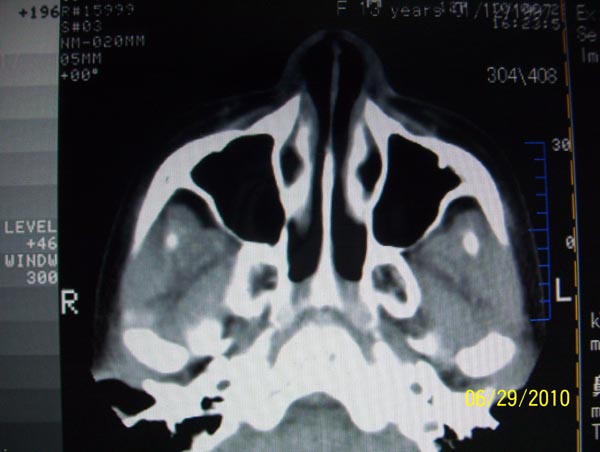

以下是引用随光逐影在2010-6-29 22:28:00的发言:[br]1)右侧下鼻甲肥大(或息肉样变)。2)鼻咽腺样体肥大。

以下是引用随光逐影在2010-6-29 22:28:00的发言:[br]1)右侧下鼻甲肥大(或息肉样变)。2)鼻咽腺样体肥大。

以下是引用随光逐影在2010-6-29 22:28:00的发言:[br]1)右侧下鼻甲肥大(或息肉样变)。2)鼻咽腺样体肥大。

以下是引用拾荒者在2010-6-30 19:22:00的发言:[br]右侧下鼻甲粘膜肥厚,鼻腔阻塞,鼻旁窦窦腔清晰,支持考虑慢性鼻炎。